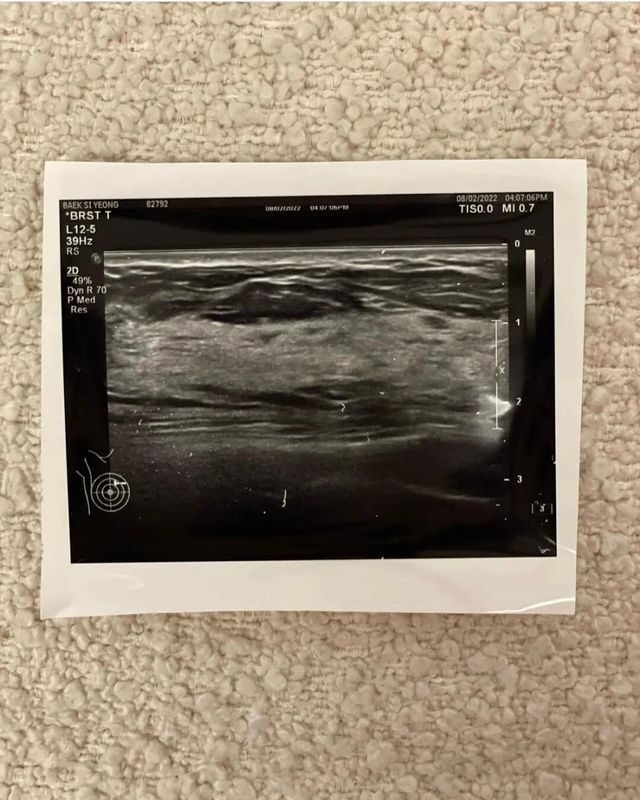

인스타 팔로우 50만명이 넘는 @si.young은 최근 자신의 인스타의 하나의 게시물을 공유했습니다. 많은 네티즌들 사이에서 확대 수술 의혹이 퍼지기 시작하면서 자신의 자연산을 증명하기 위해서 병원의 진단서와 함께 초음파 검사 결과를 공유한 것이었죠.